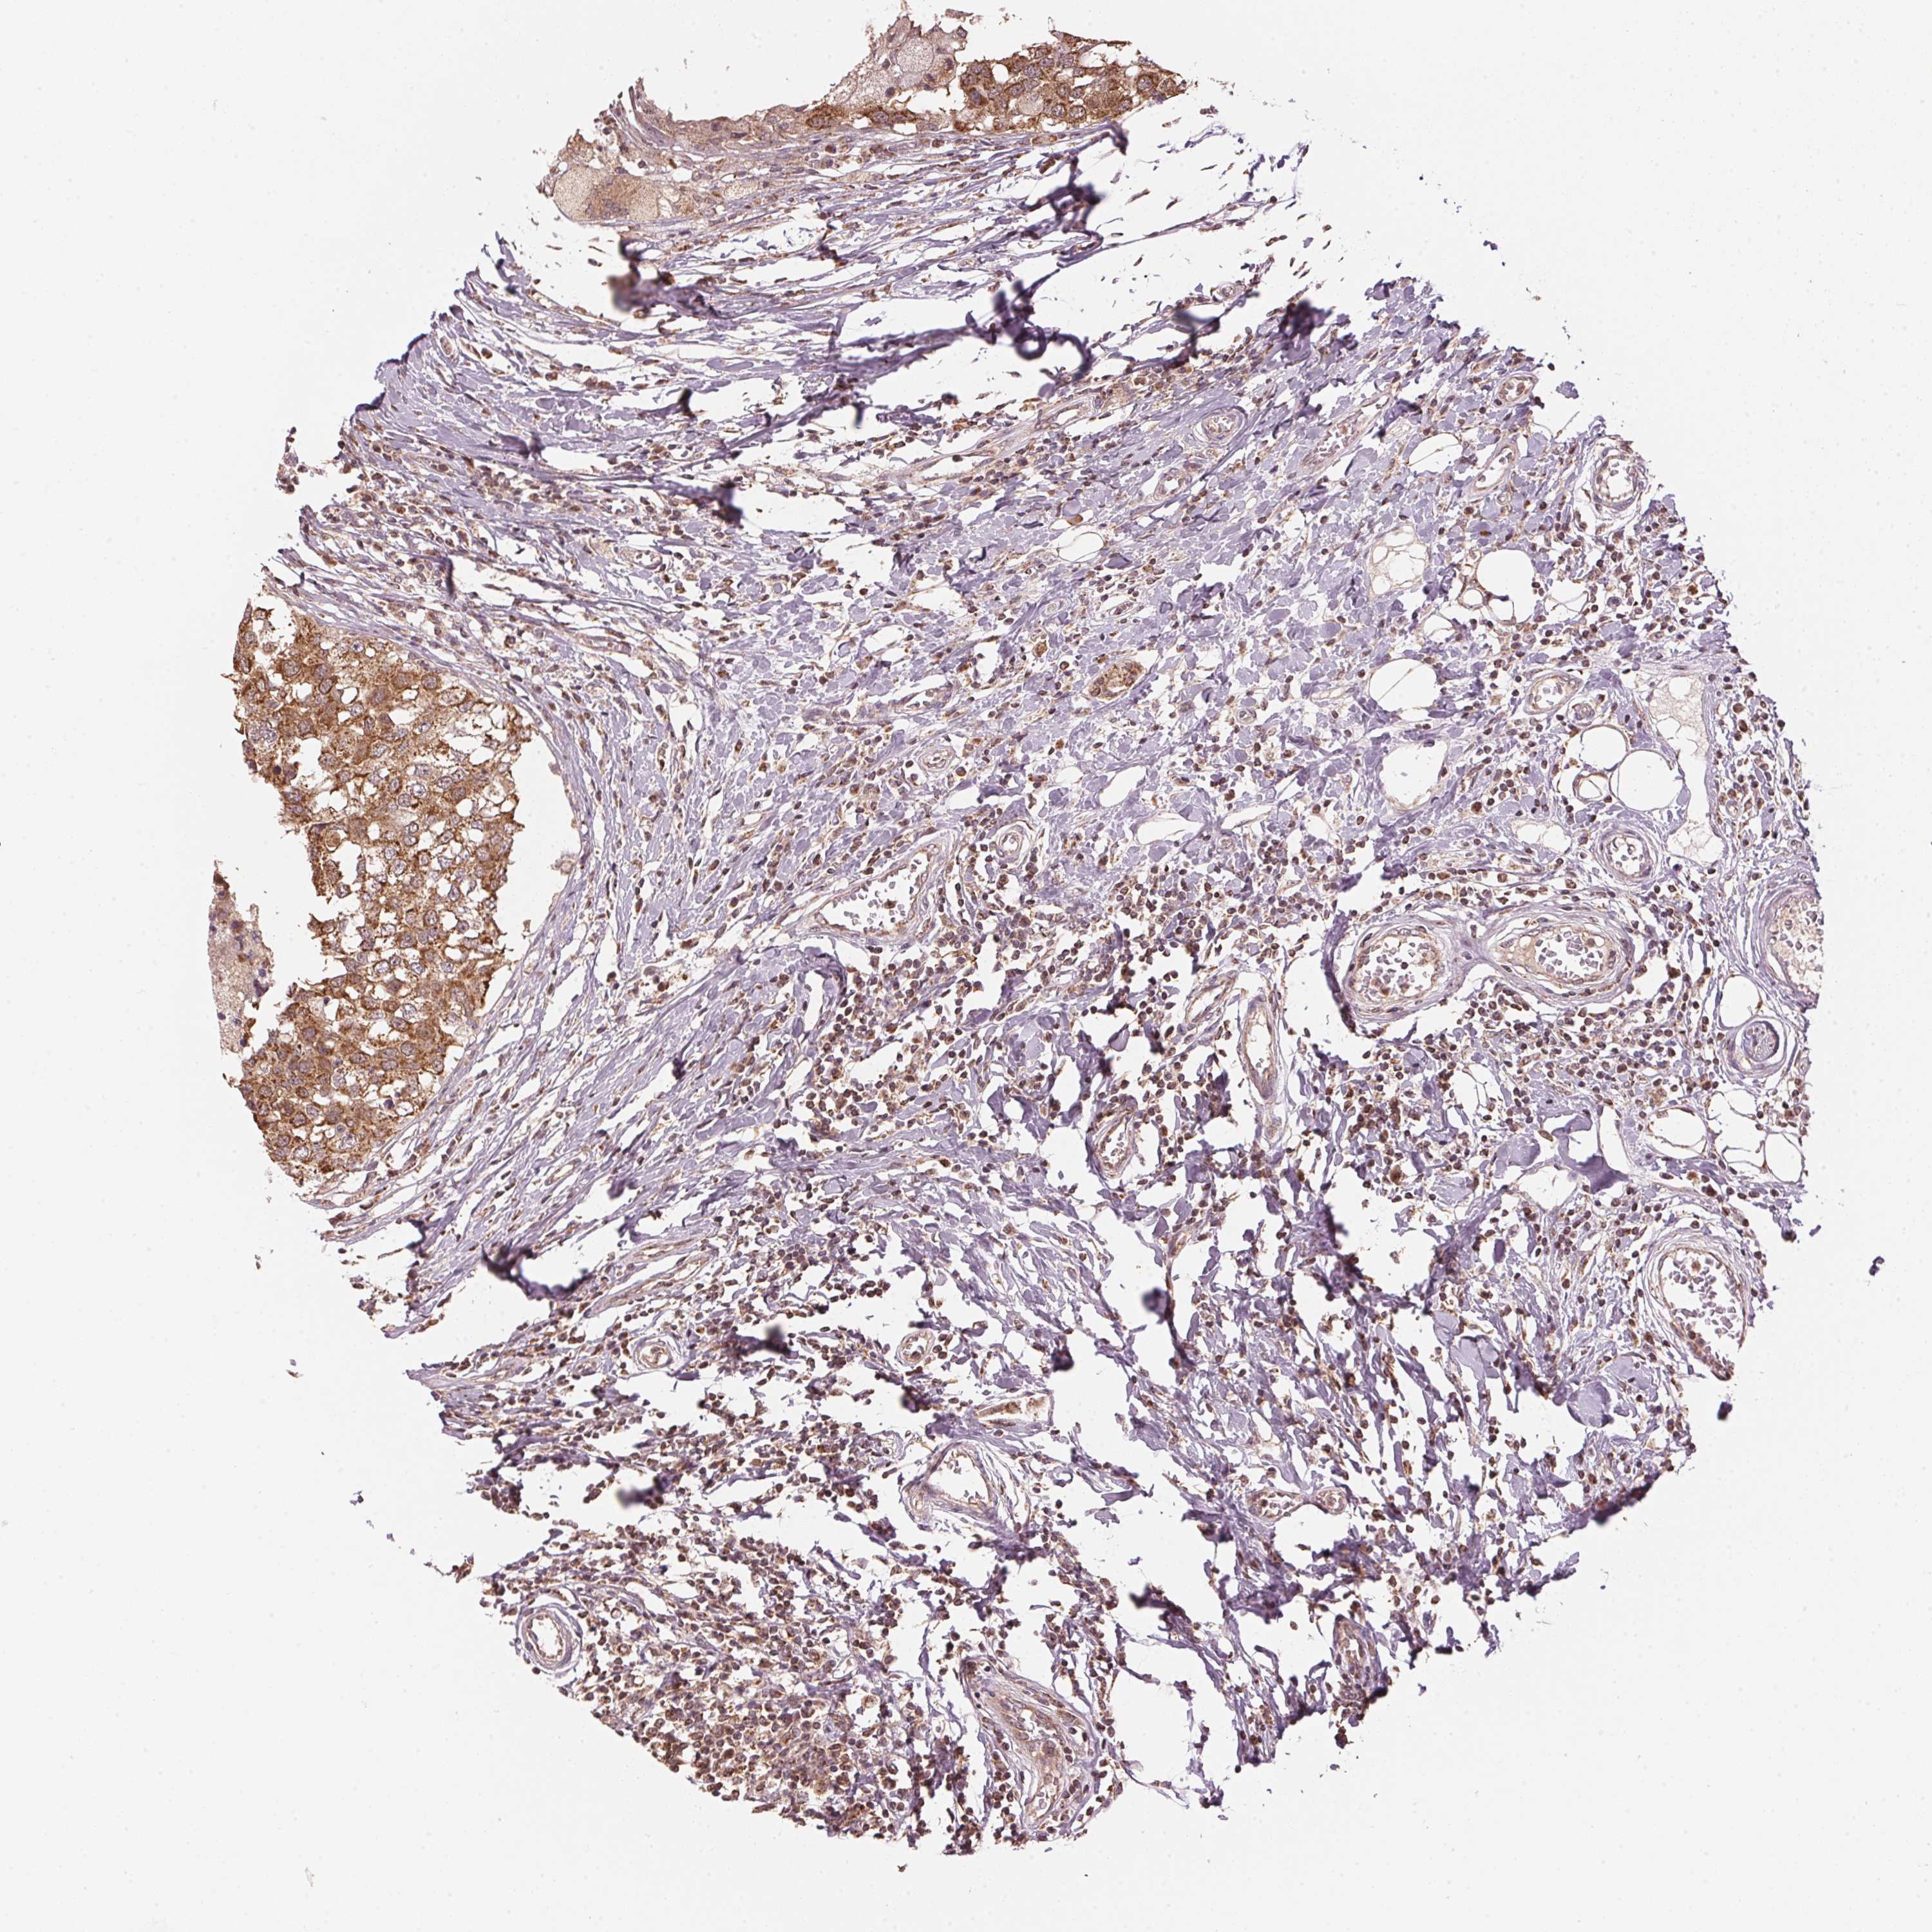

BRCA TCGA BRCA VALIDATION PROTEIN EXPRESSION

Breast cancer

Human cancer